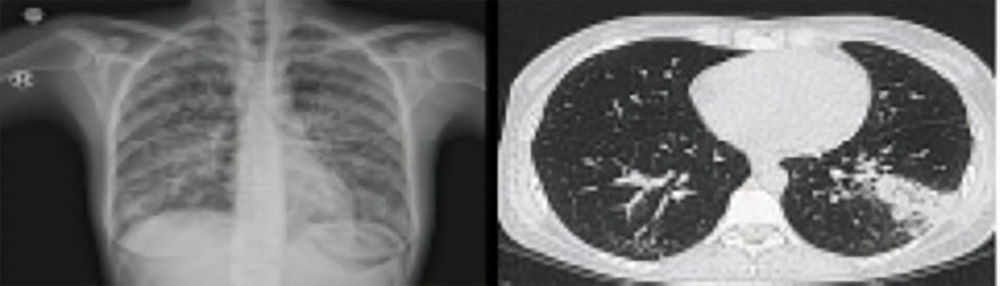

Further anamnesis revealed that the skin lesions had been present for approximately one month and had not responded to topical treatments. Posteroanterior chest radiography revealed diffuse bilateral opacities (Figure 1). Despite receiving broad-spectrum antibiotics, including meropenem, linezolid, and tigecycline for one week at the external center, the patient’s fever persisted. Given the clinical presentation and immunosuppressed status, empirical therapy with liposomal amphotericin B (3 mg/kg/day), ganciclovir (5 mg/kg twice daily), moxifloxacin (400 mg/day), and dexamethasone (6 mg/day) was initiated.

Although the patient’s clinical condition had improved significantly, persistent bilateral pulmonary opacities on chest radiography prompted high-resolution computed tomography (HRCT), which revealed 24 mm lymphadenopathy in the left hilar region, nodular consolidation in the superior segment of the left lower lobe, and fibrotic changes in the right lower lobe (Figure 1). These findings raised suspicion of primary tuberculosis, and bronchoscopy was performed.

Figure 1. Chest X-ray and high-resolution tomography images of the patient